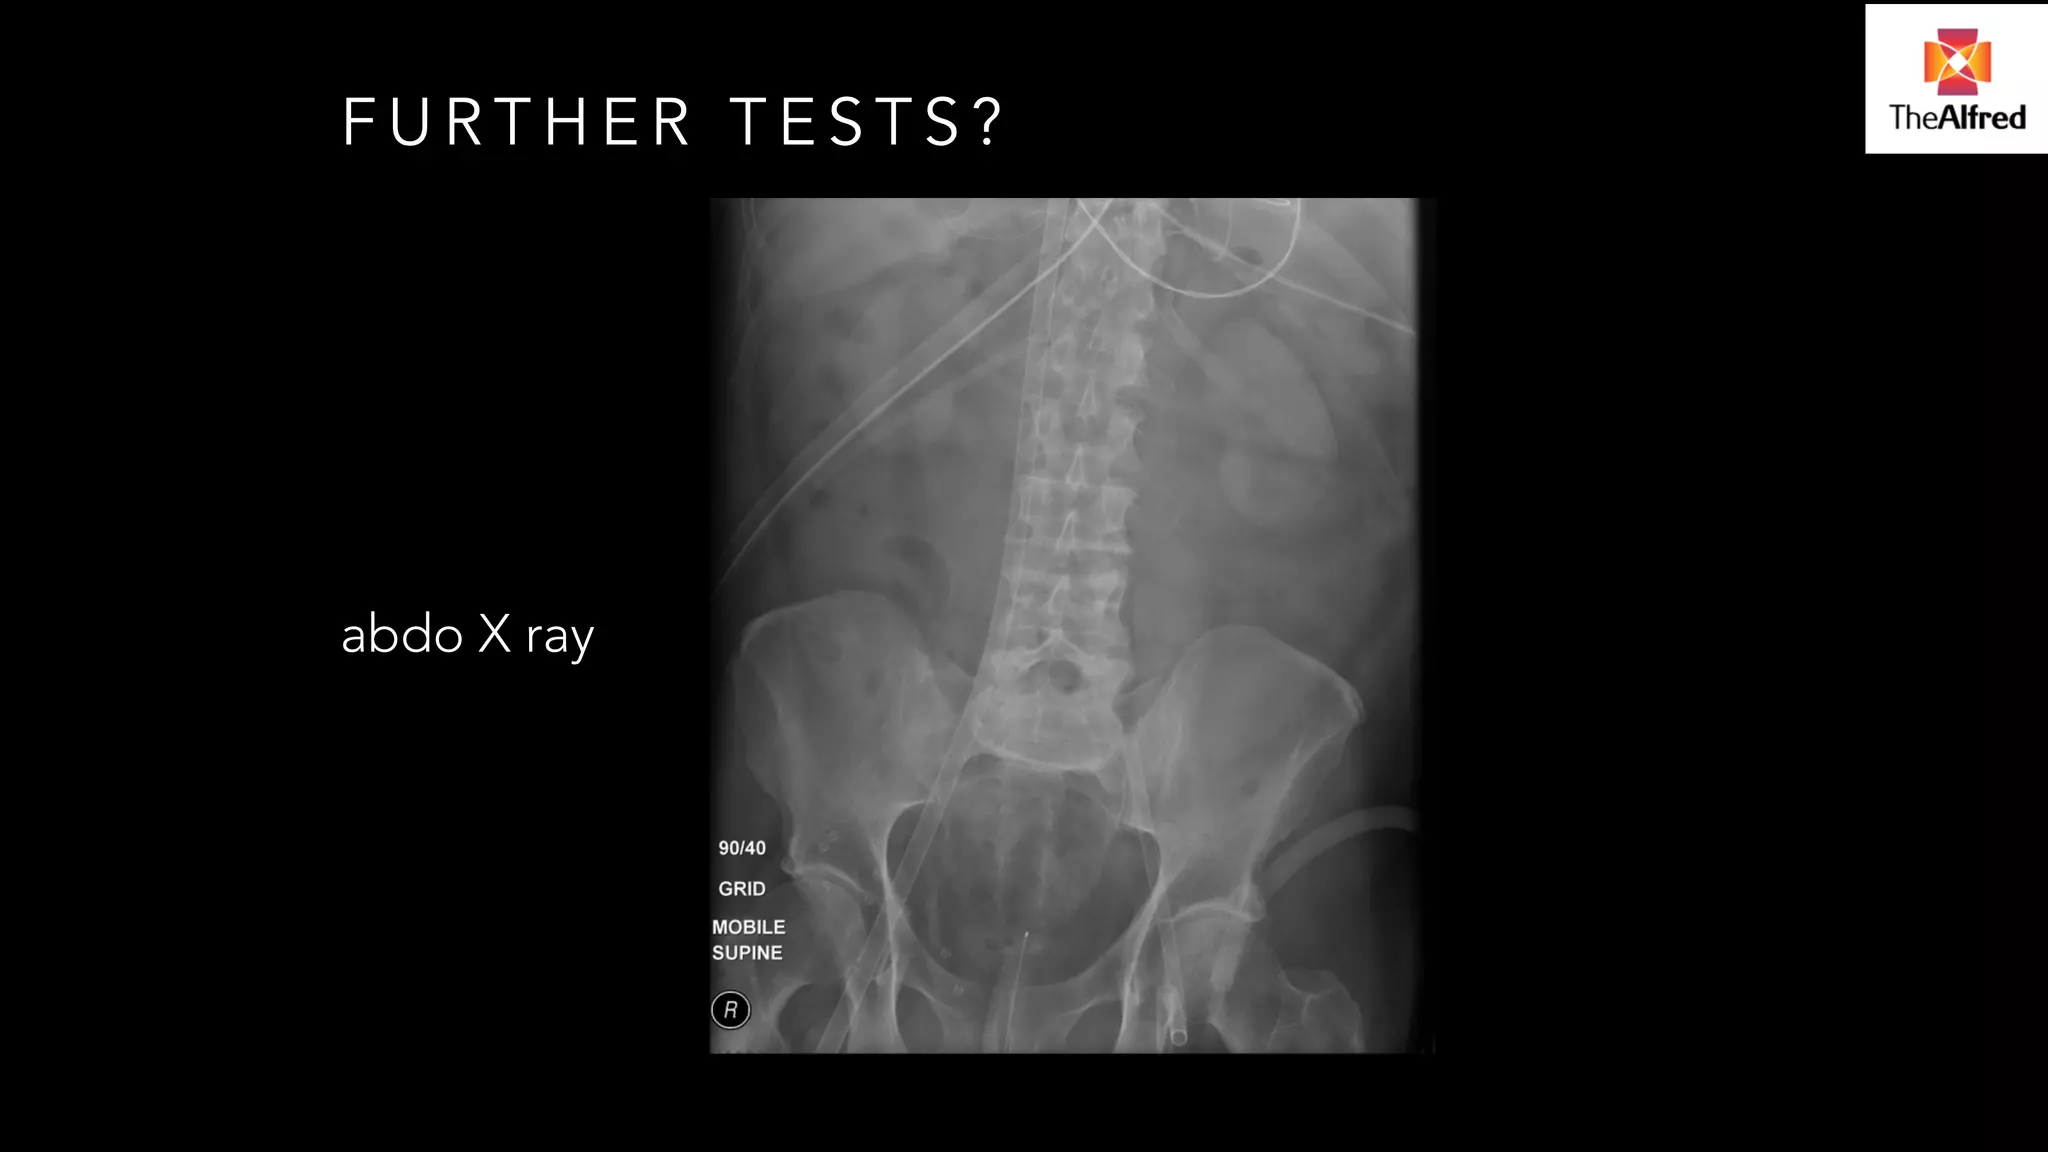

FURTHER TESTS?

abdo X ray